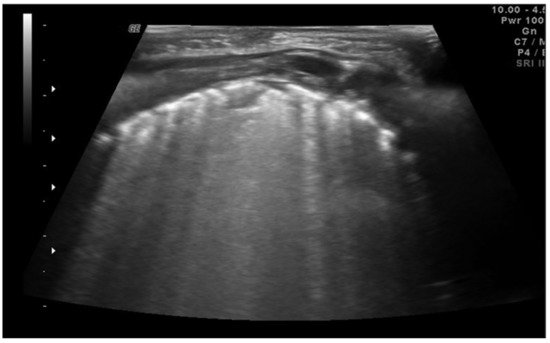

“A-lines” represent some of these artifacts that can be found in a completely healthy lung (Figure 1) [7]. They are horizontal echogenic lines equidistant and parallel to each other and the pleura, representing reverberations of the pleura itself that arise when the ultrasound beam reflects off of the pleura and partially reflects off of the probe face back to the pleura again before getting back to the machine instead of entering the probe. They are caused by the large difference in acoustic impedance between the pleura and the air contained in the lungs. The distance from each other is related to the distance between the pleural line and the skin surface, and their position does not change with respiratory acts.

Figure 1. Appearance of a healthy lung. White arrows show pleural and A-lines.